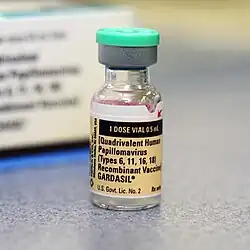

Vaccination

About 90% of HPV+OPC carry HPV 16, and another 5% HPV 18. These two types are both targets of available vaccines. HPV vaccines given before exposure can prevent persistent genital infection and the consequent precancerous state.[11] Therefore, they have a theoretical potential to prevent oral HPV infection.[8] A 2010 review study has found that HPV16 oral infection was rare (1.3%) among the 3,977 healthy subjects analyzed.[85]